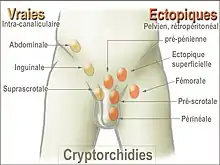

A testis absent from the normal scrotal position may be:

- Anywhere along the "path of descent" from high in the posterior (retroperitoneal) abdomen, just below the kidney, to the inguinal ring

- In the inguinal canal

- Ectopic, having "wandered" from the path of descent, usually outside the inguinal canal and sometimes even under the skin of the thigh, the perineum, the opposite scrotum, or the femoral canal

- Undeveloped (hypoplastic) or severely abnormal (dysgenetic)

- Missing (also see anorchia).

About two-thirds of cases without other abnormalities are unilateral; most of the other third involve both testes. In 90% of cases, an undescended testis can be felt in the inguinal canal. In a small minority of cases, missing testes may be found in the abdomen or appear to be nonexistent (truly "hidden").